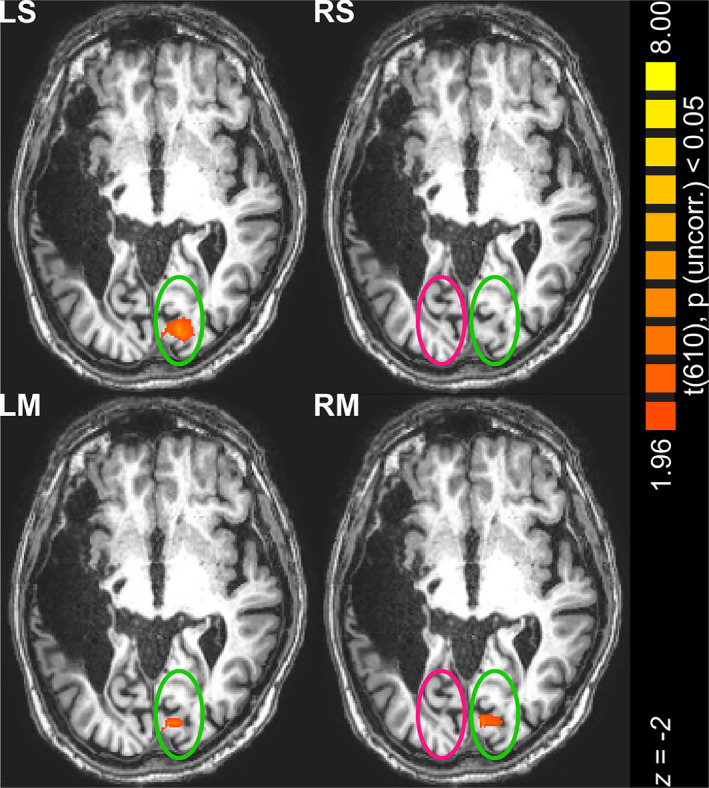

Patients with lesions in the visual cortex are blind in corresponding regions of the visual field, but they still may process visual information, a phenomenon referred to as residual vision or "blindsight". Here we report behavioral and fMRI observations with a patient who reports conscious vision across an extended area of blindness for moving, but not for stationary stimuli. This completion effect is shown to be of perceptual and not of conceptual origin, most likely mediated by spared representations of the visual field in the striate cortex. The neural output to extra-striate areas from regions of the deafferented striate cortex is apparently still intact; this is, for instance, indicated by preserved size constancy of visually completed stimuli. Neural responses as measured with fMRI reveal an activation only for moving stimuli, but importantly on the ipsilateral side of the brain. In a conceptual model this shift of activation to the "wrong" hemisphere is explained on the basis of an imbalance of excitatory and inhibitory interactions within and between the striate cortices due to the brain injury. The observed neuroplasticity indicated by this shift together with the behavioral observations provide important new insights into the functional architecture of the human visual system and provide new insight into the concept of consciousness.